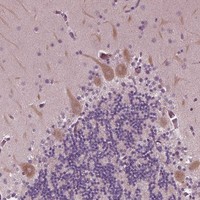

Cytoplasmic expression in neuronal cells, including Purkinje cells.

Cerebral cortex

Cerebellum